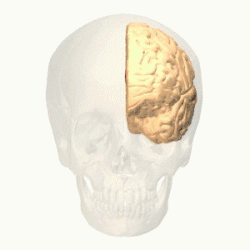

Prefrontal cortex

The prefrontal cortex (PFC) is responsible for complex cognitive behaviour, decision making and consciousness (Burton, Westen, Kowalski, & Westen, 2015). While there is still much debate as to what specific role the different areas of the PFC play in anxiety related disorders, a review conducted by Spalding in 2018, investigated the role that the medial prefrontal cortex (mPFC) has in relation to fear generalisation - conditioned fear generalising to related stimuli, (Spalding, 2018). The study found that in human subjects, the ventral mPFC plays an important role in inhibiting the fear generalisation, while dorsal mPFC is seen to activate fear generalisation. Studies indicate that "higher levels of anxiety have been associated with increased activity in the dorsal mPFC (Straube et al., 2009), but further research needs to be done to investigate this.